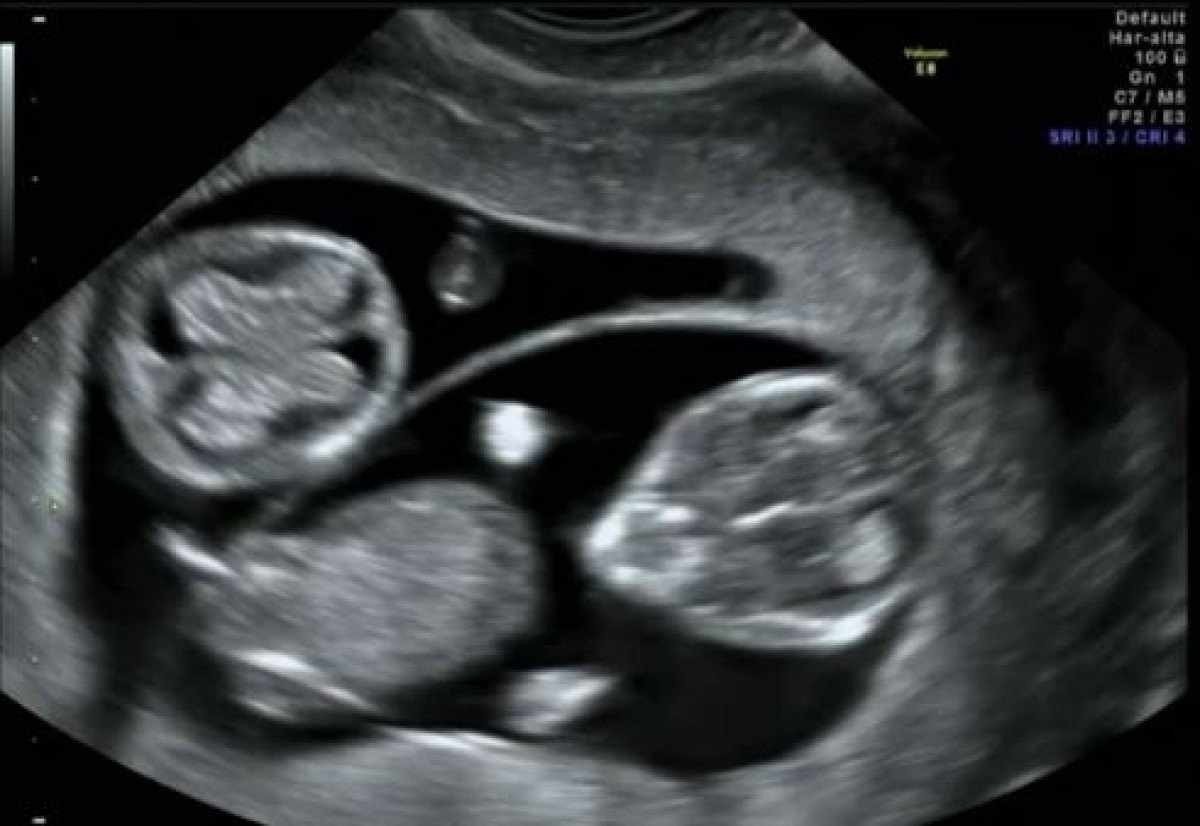

De acordo com a história revelada pela Revista crescer, o primeiro ultrassom feito por Roseni mostrou uma gravidez de gêmeos. Depois, no segundo exame apareceu mais um feto: eram trigêmeos. Foi somente no terceiro ultrassom que o quarto bebê apareceu e revelou a gravidez de quadrigêmeos.

Roseni da Silva, 38 anos, está grávida de 33 semanas e disse que foi assustador descobrir a gestação de quatro bebês

Roseni da Silva, 38 anos, está grávida de 33 semanas e disse que foi assustador descobrir a gestação de quatro bebês (foto: Reprodução/TikTok evertonleite278)